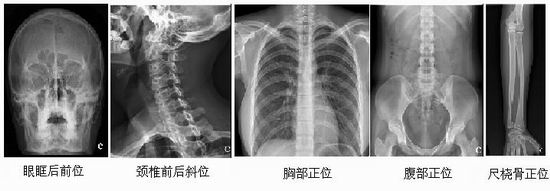

主要功能:飞利浦的Digital Diagnost VR采用了最先进的探测器技术,具有ISO800的感光灵敏度,极佳的光量子转换效率,可以以较低的剂量获得高质量的图像,既能减少X线对操作者和患者的损伤,又延长了球管的使用寿命。采用DDR动态范围扩展图像处理软件,最大限度地增加了影像的动态密度范围,严格保持信息的正确性,不会产生伪影,为医生获得丰富的诊断信息。系统极高的自动化操作系统,快速显示图像信息,无需等待,极大地提高了工作效率和病人检查速度。